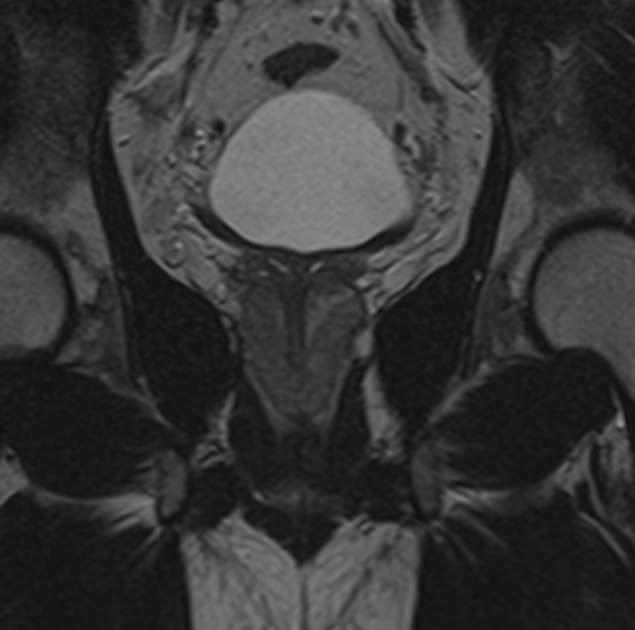

Магнитно-резонансная томография органов малого таза у мужчин подразумевает послойное сканирование анатомической зоны предстательной железы, мочевого пузыря с мочеточниками, прямой кишки и полости малого таза с окружающими мягкими тканями.

структуру предстательной железы, а также выявить происходящее в ней патологические процессы. К примеру, для таких заболеваний, как простатит, аденома простаты (доброкачественная гиперплазия) и рак простаты очень важна ранняя диагностика, что и позволяет МРТ. Для обследования простаты метод МРТ является уникальным по своей информативности.

Кроме предстательной железы при исследовании визуализируются семенные пузырьки, семявыводящие протоки.